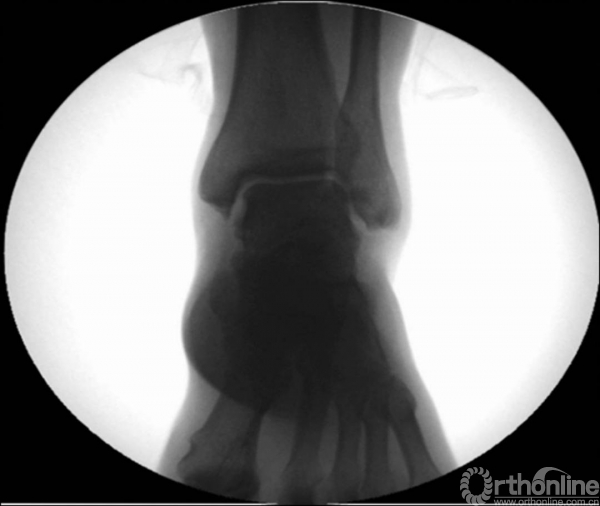

X线诊断:标准的踝关节影像学评估应包括3个位相:前后位(图5),踝穴位(内旋15°)(图6),侧位(图7)。

图5 前后位

当踝关节严重损伤时内外踝及距骨将发生不同程度的移位(图8)。有时外踝骨折会伴有三角韧带的损伤,静态的X线摄片并不能准确地反映踝关节的稳定性,应力位片及MRI检查可完善对踝关节稳定性及韧带损伤的评估(图9)。此时应通过患肢损伤机制及放射资料准确判断踝关节损伤的类型以正确指导复位和固定。有时单纯内踝骨折可能是更为复杂的“Maisonneuve骨折”的一部分,该骨折还包括腓骨近端骨折及韧带联合损伤,故X线检查应投照整个胫腓骨。

图8 骨折移位明显合并有脱位